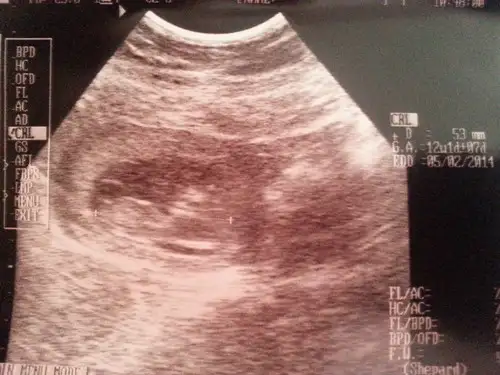

dr soylemeden siz gorun genital nub teorisi ( bebegin cinsiyeti)

iğne ucu gibi pipi altta testis ...ay bi hoş oldummmmm .....ben de istiyorum o minicik pipiden ama kısmet Allah büyük bu 3. bebişim 2 kızım var bu da erkek olsa işallah ...çok istiyorum çokkkkk....

bendeeee...bizim de babacı bir kızımız var..anneci bi oğlum olsun ne kadar çok isterdim...ben bebişin nubunu ekranda gördüm.doktor bize önce kız dedi.sonra 'bakın beyefendiciğim bi çıkıntı var erkekte olabilir' dedi ve bi çıkıntı gösterdi ama paralel miydi dik miydi anlamadım.heycandan fotoğrafını da istemedim...

çok ilginç bi yöntem...bunu bütün doktorların biliyor olması gerekmez mi??bizimki 16. haftadan önce kesinlikle söylemiyor